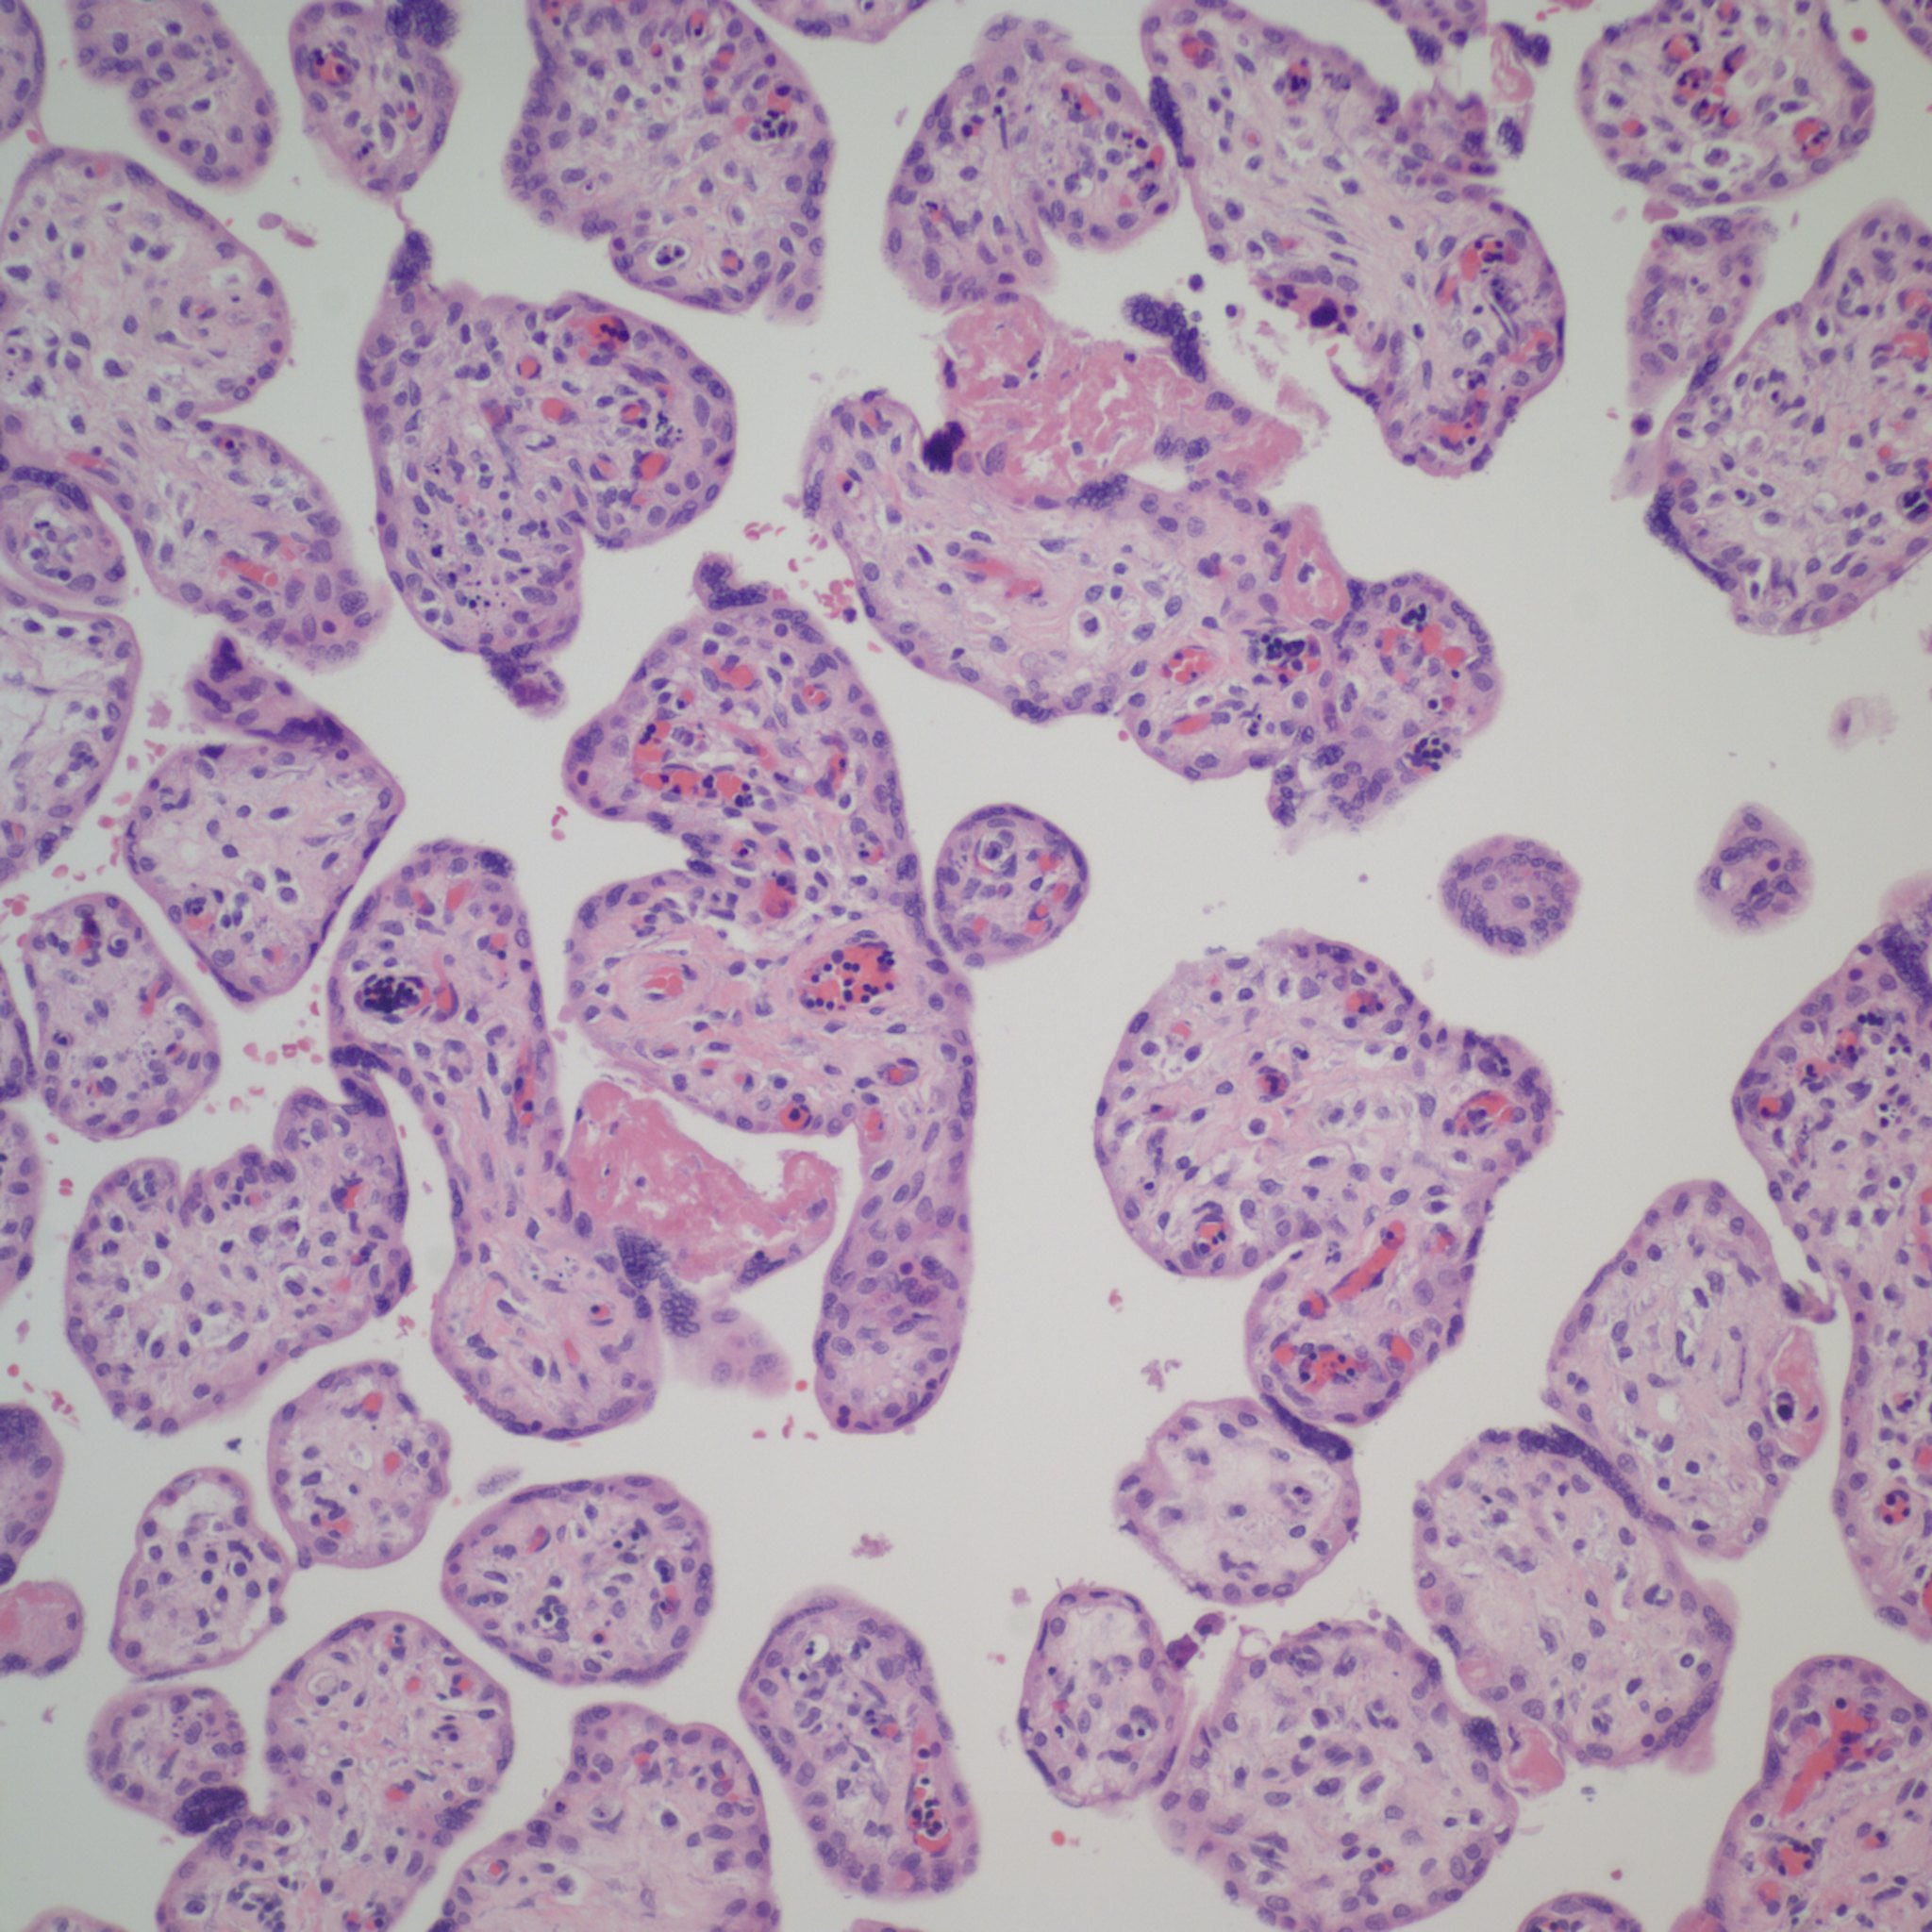

The placental examination demonstrated a marked erythroblastosis (Fig 1). There was mild hydrops. There were no intranuclear inclusions typical of Parvo virus in the nucleated red blood cells, and an immunostain for Parvo virus was negative.

[caption id="attachment_58" align="alignnone" width="300"]

Spleen, left H&E 20x, right iron stain 40s showing pale hemosiderin macrophages.

Kidney showing hematopoiesis around a vessel, H&E 20x[/caption]